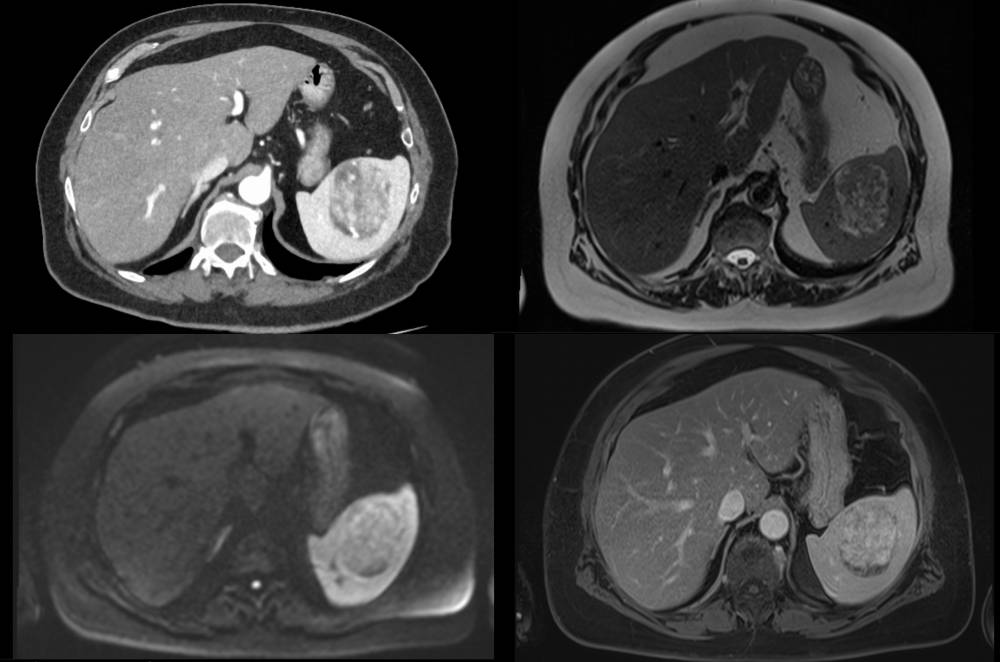

Ein CT- und MRT-Scan des menschlichen Bauchs, wahrscheinlich zur Untersuchung eines Organs.

Hepatobiliär-pankreatische Radiologie

Die internistische abdominelle Radiologie befasst sich mit der Diagnostik von Leber, Gallenwegen, Bauchspeicheldrüse (Pankreas), Milz und Gastrointestinaltrakt. Neben Sonographie und radiographischen Verfahren sind Computertomographie und Magnetresonanztomograhie die beiden Eckpfeiler der radiologischen Diagnostik. Aufgrund anatomischer und pathologischer Komplexität und prognostischer Faktoren besitzen hier Untersuchungen der Leber, der Gallenwege und der Bauchspeicheldrüse einen besonderen diagnostischen Stellenwert. So ist die Bildgebung gutartiger oder bösartiger neoplastischer Erkrankungen mit Tumoren der genannten Organe neben der Pathologie häufig diagnostischer Goldstandard. Diese Patienten werden in einer dezidierten subspezialisierten Fachkonferenz adressiert, die unseren onkologischen Fachkonferenzen vorgeschaltet ist. Dort wird neben zusätzlich erforderlichen Untersuchungen im Rahmen der Ausbreitungsdiagnostik (Staging) mit Expertinnen und Experten der Viszeralchirurgie, Inneren Medizin (Gastroenterologie), Onkologie, Strahlentherapie, Nuklearmedizin und Pathologie ein individualisiertes und leitliniengerechtes Therapiekonzept beschlossen.

Zu unseren Spezialkompetenzen zählen:

• Tumoren der Leber

Neben der Diagnostik gehören die einschlägigen bildgestützten Interventionen (Biopsien, Drainagen, Mikrowellenablationen) zu unseren Leistungsschwerpunkten. Neben minimalinvasiven Kathetermethoden können wir mit thermoablativen Verfahren neoplastische Läsionen (z.B. in der Leber) hochpräzise lokal behandeln. Diese Verfahren sind zusätzlich zur chirurgischen und medikamentösen Behandlung der dritte Pfeiler einer optimalen, individualisierten Tumortherapie.